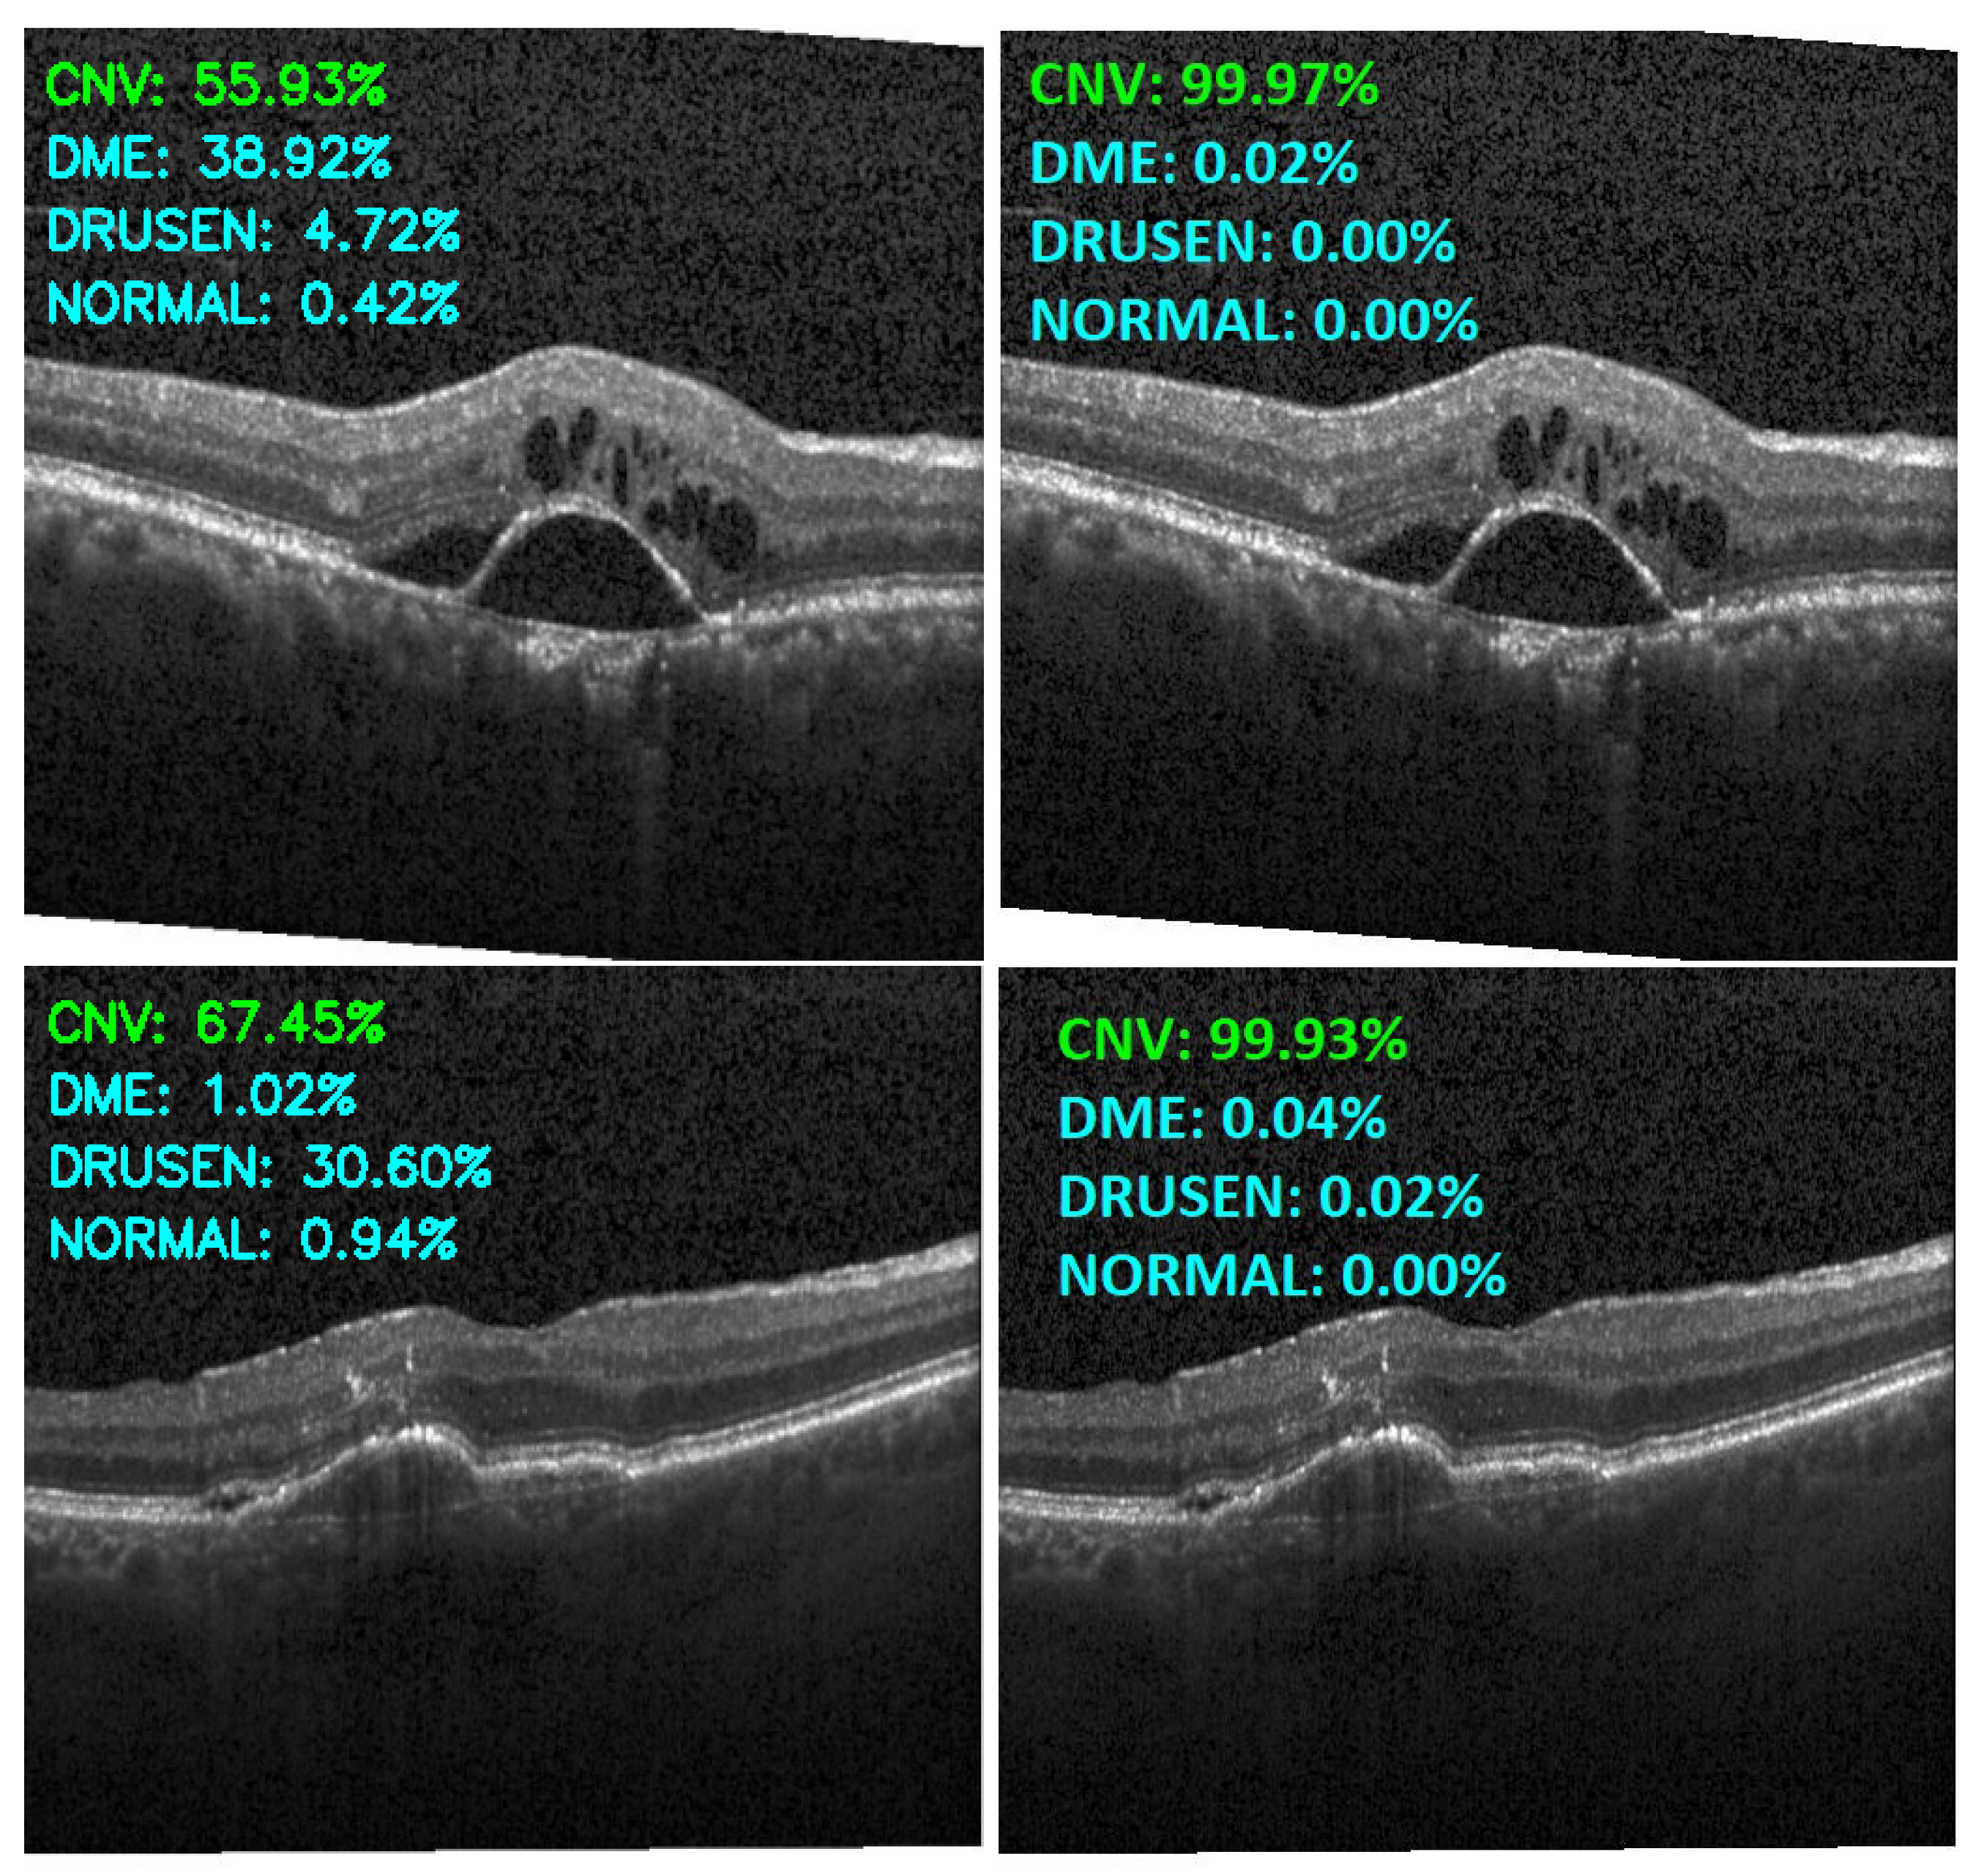

Figure 13, Figure 14, Figure 15 and Figure 16 show several examples of the proposed model performance (accuracy and classification confidence score) on OCT images using the original and augmented dataset-trained model, respectively.

Figure 13.

Exemplary result of proposed model trained without (left column) and with (right column) augmentation (correct label highlighted in green).